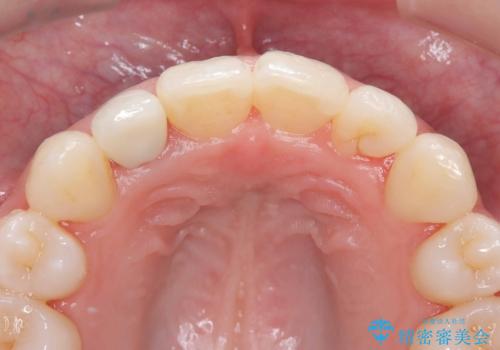

オールセラミッククラウンで治療を行いました。

被せ物と歯の境の位置が歯肉の上に設定されており、それによって審美障害が起きていました。

歯と被せ物の境を歯肉縁下0.5㎜に設定して形成を行いオールセラミッククラウン(スペシャル)で治療を行いました。